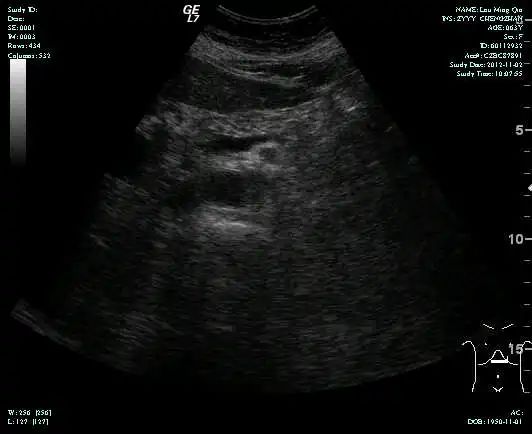

CT-T

CT-H1

MR-H1

影像学检查结果评估:cPD。